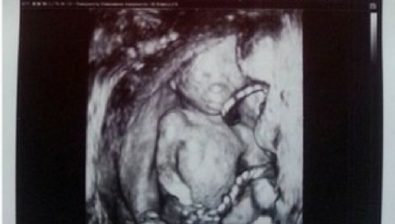

Ultrasound at 16 Weeks

There are now fine lanugo hairs covering your baby’s body and head. Of course, it’s too fine to see via an ultrasound, but it’s there nonetheless.

The umbilical cord might appear to have a lower placement on your baby’s abdomen this week.

You’ll be delighted to know that your baby’s tiny fingernails that started to develop earlier are now well-formed.